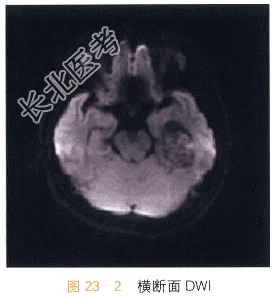

- [材料题] 女,53岁,头痛20天。影像学资料如图23-1~图23-4所示。

读片分析:头颅CT平扫显示左侧侧脑室颞角扩大,内可见不规则形高密度影;MRI检查横断面T₂WI示第三脑室内不规则形异常软组织肿块影,T₂WI等高信号,信号混杂不均,边界尚清晰;DWI呈等信号;增强扫描肿块明显强化,表面呈颗粒状。